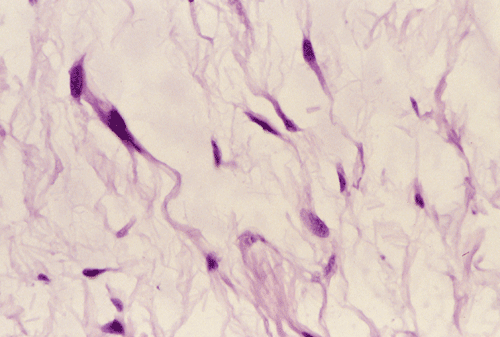

Panel A, B, and C are taken from the one area. Panel D, E, F, and G are taken from another area. Panel H and I are taken from areas with similar histologic features but distinctly separately on the same slide.

On low-magnifaction (Panel A and D), the lesional tissue appears to have generalized myomatous changes. No entrapped skeletal muscle fibers are found. The tumor cells tended to group into areas with variable cellularity that range from low- to, at most, moderate-cellularity. The hypocellular areas (Panel  B and C) contain sparsely spaced bland spindle cells in a bluish myxomatous background. The nuclei are elongated and mostly normochromatic. A few hyperchromatic nuclei are present and they are compatible with degenerative atypia (ancient change).

Islands with increased cellularity are present in some areas (Panel D, E, F, and G). These islands comprise about 30-40% of the lesional tissue. The cytologic features of the tumor cells in these areas are almost identical to that of the hypocellular areas except that the cellularity was increased. No mitotic figures are found in these areas. Focal hypervascularity are often found in areas with hypercellularity. No cellular condensation around blood vessels are noted (Panel  H and I).